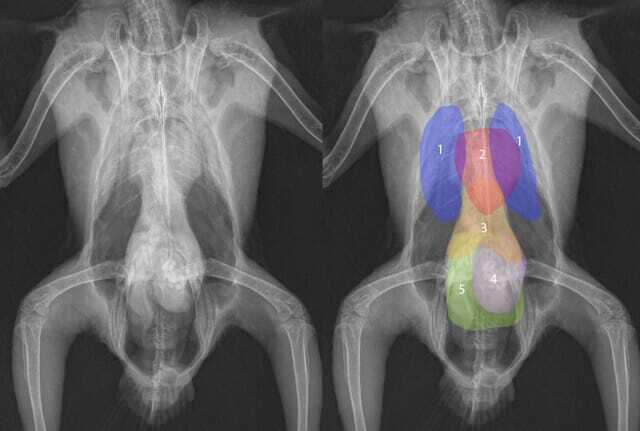

The normal anatomy of birds varies greatly depending on the species, age and sex of the patient; however, a general interpretation should follow the same pattern every time to ensure nothing has been overlooked when assessing the images (Figures 4 and 5).

Cardiovascular system

The heart can be visualised in the cranial coelomic cavity on ventrodorsal and lateral views. In captive psittacines, the heart base should be within 51 to 61 percent of the maximum width of the thorax on ventrodorsal view (Crosta et al., 2018). However, species-specific values should be referenced when assessing for cardiomegaly. In the VD

view, the cardiac silhouette contributes to the “hourglass figure” described by many resources. The great vessels can be identified on both views as soft tissue opacities, as round “dots” on the ventrodorsal view and as more recognisable longitudinal structures on the lateral views.

Respiratory system

Birds have fixed, dorsal lungs, which are best evaluated on a lateral view. These sit dorsal to the heart and have a characteristic honeycomb appearance, due to the presence of parabronchi. The trachea can be easily traced from the skull down to where it bifurcates at the syrinx. The syrinx is a common place for fungal lesions to form in captive psittacines, so the area should be assessed for any abnormal soft tissue opacities. Air sacs are thin and should be empty of anything other than air, and so are best evaluated by their borders with other organs. They are visible on the ventrodorsal views lateral to the hepatic silhouette. The walls of air sacs should not be identifiable, so increase in wall thickness should rouse suspicion of air sacculitis.

Digestive system

The avian digestive system consists of the crop (with the exception of some species), proventriculus, ventriculus or gizzard, intestines, caecum and cloaca. It is best examined by use of contrast media, due to superimposition of the caudal coelomic contents. Ideally, patients are starved long enough before general anaesthesia to allow food to move distally from the crop; however, sometimes food can be visualised inside. The proventriculus sits dorsally and caudal to the heart on the lateral view. Abnormal distention of the proventriculus can be an indication of proventricular dilatation disease (PDD) and should be followed up with contrast radiographs.

The ventriculus or gizzard normally contains some grit with opacity similar to that of bone. Metal opacity particles within the ventriculus should not be present and should result in a suspicion of metal ingestion (Figure 6). The ventriculus sits caudoventrally to the proventriculus on the lateral view and slightly to the left of midline on a ventrodorsal projection. The intestines, caecum and cloaca are superimposed on other coelomic organ and so can only be fully evaluated with contrast media.

Other coelomic viscera

The liver is best assessed on the ventrodorsal view, where it should form a rough hourglass shape when viewed in conjunction with the heart. As a general rule, the edges of the hepatic silhouette should not extend laterally past an imaginary line between the shoulder joints and the acetabulae of the hips.

The spleen is best visualised on a lateral view, where it is seen as a round, soft tissue opacity dorsal to the liver and proventriculus. The kidneys are also best visualised on the lateral view, sitting dorsally within the pelvis. They are often only seen as soft tissue opacities, so any increase in radiopacity should be further investigated.

The gonads of birds are internal and superimpose upon the cranial pole of the kidneys. Their size depends on the reproductive status of the patient at the time. Males have bilateral testes and in females only the left ovary is functional.